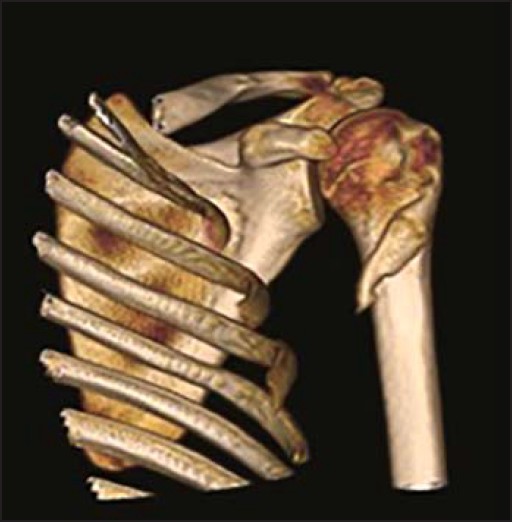

Initial X-ray and MR images were taken 3.5 months after the injury at an outside institution. The X-ray demonstrated an ossifying mass in the upper third of the arm within the pectoralis major muscle that coalesced with the underlying humerus [Figure 1]. The MRI showed some zoning phenomenon especially on the coronal T1 scan [Figure 2] and the water sensitive sequences also showed some swelling and high signal around the mass. A second series of imaging X-ray [Figure 3]a and b and CT scan [Figure 4] at 5 months showed further maturation especially of the outer compact bone of the mass with resolution of the surrounding soft tissue swelling at the insertion of the pectoralis major muscle. | Figure 1: AP X-ray of shoulder at 3.5 months showing an ossifying mass coalescing with the proximal humerus

| Figure 4: 3D CT scan of shoulder at 5 months demonstrating a fully mature myositis ossificans

After a significant traumatic injury to a muscle, bleeding occurs into or around it. The resulting hematoma undergoes organization and mineralization from the outside in. This reflects the 'zoning phenomenon' characteristically seen with myositis ossificans in which three distinct zones have been classified. [1] The central zone is made up of fibroblasts and necrotic muscle; the middle zone has osteoblasts and immature bone and the most peripheral zone is formed of mature trabeculoid distinct from the surrounding tissue. This shows on films as a well-circumscribed mass with an outer layer of ossification and a lucent centre. Depending on the level of maturation of the lesion, all three zones might not always be clearly demonstrated radiographically. Calcification of the lesion is seen as early as 11 days up to 4 weeks. Ossification and formation of a sharp circumscribed mass occur at 4-8 weeks, and the lesion reaches full maturity after 5 months. [1]

Standard radiographs often appear normal during the early stages of myositis ossificans but can show de novo pathognomonic ossification surrounding a clear central area at a later stage. [2] Some reports suggest ultrasound to be the most sensitive imaging modality to detect early zone phenomenon in myositis ossificans. [15] MRI may show the so-called zone phenomenon even before the ossification appears. CT scans are more sensitive than radiography for detecting ossification and may also show a central fatty metaplastic area. [16]